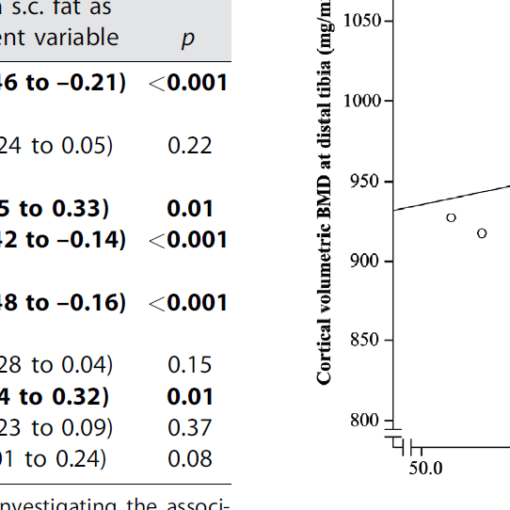

Densitometry and imaging techniques are currently used in clinical settings to measure bone quantity and spatial structure. Recently, Reference Point Indentation has opened the possibility of directly assessing the mechanical characteristics of cortical bone in living individuals, adding a new dimension to the assessment of bone strength. Impact microindentation was specifically developed for clinical studies and has been tested in several populations where there are discrepancies between bone density and fracture propensity, such as type 2 diabetes, atypical femoral fracture, stress fractures, glucocorticoid treatment, patients with osteopenia and fragility fractures, and individuals infected with HIV, among others. Microindentation will complement, not replace, existing bone analysis methods, particularly where bone mineral density does not fully explain fracture propensity. The available evidence provides solid proof of concept; future studies will fully define the role of microindentation for the assessment of bone health both in clinics and in research.